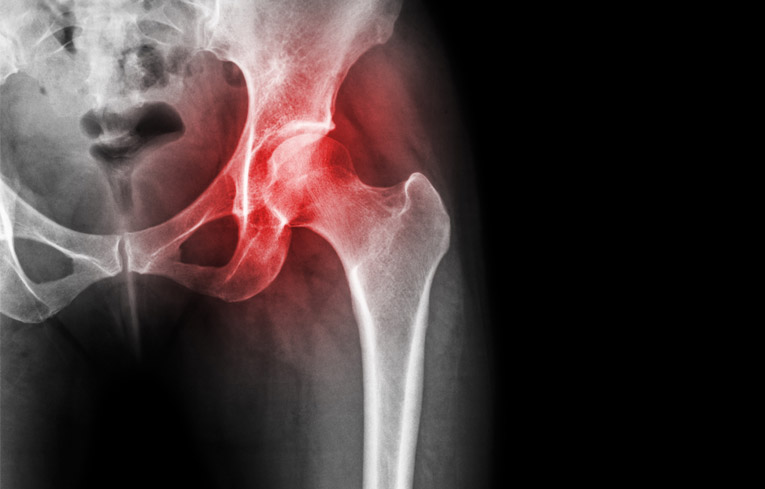

The Hip

The hip is one of the most flexible joints of the body. It is a ball and socket joint formed between the proximal end of the femur bone and the acetabulum (or the socket) of the pelvic bone. This allows us to move our legs in a wide range of motion for a number of activities.